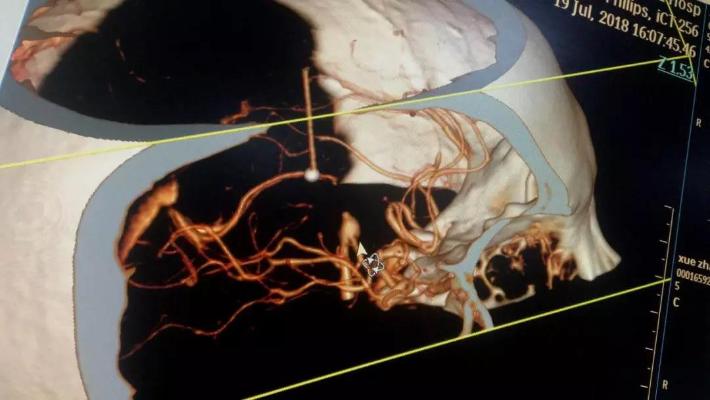

行头颈动脉CTA检查

DSA

右侧颈内动脉虹吸段夹层动脉瘤,右侧大脑前动脉A1段纤细